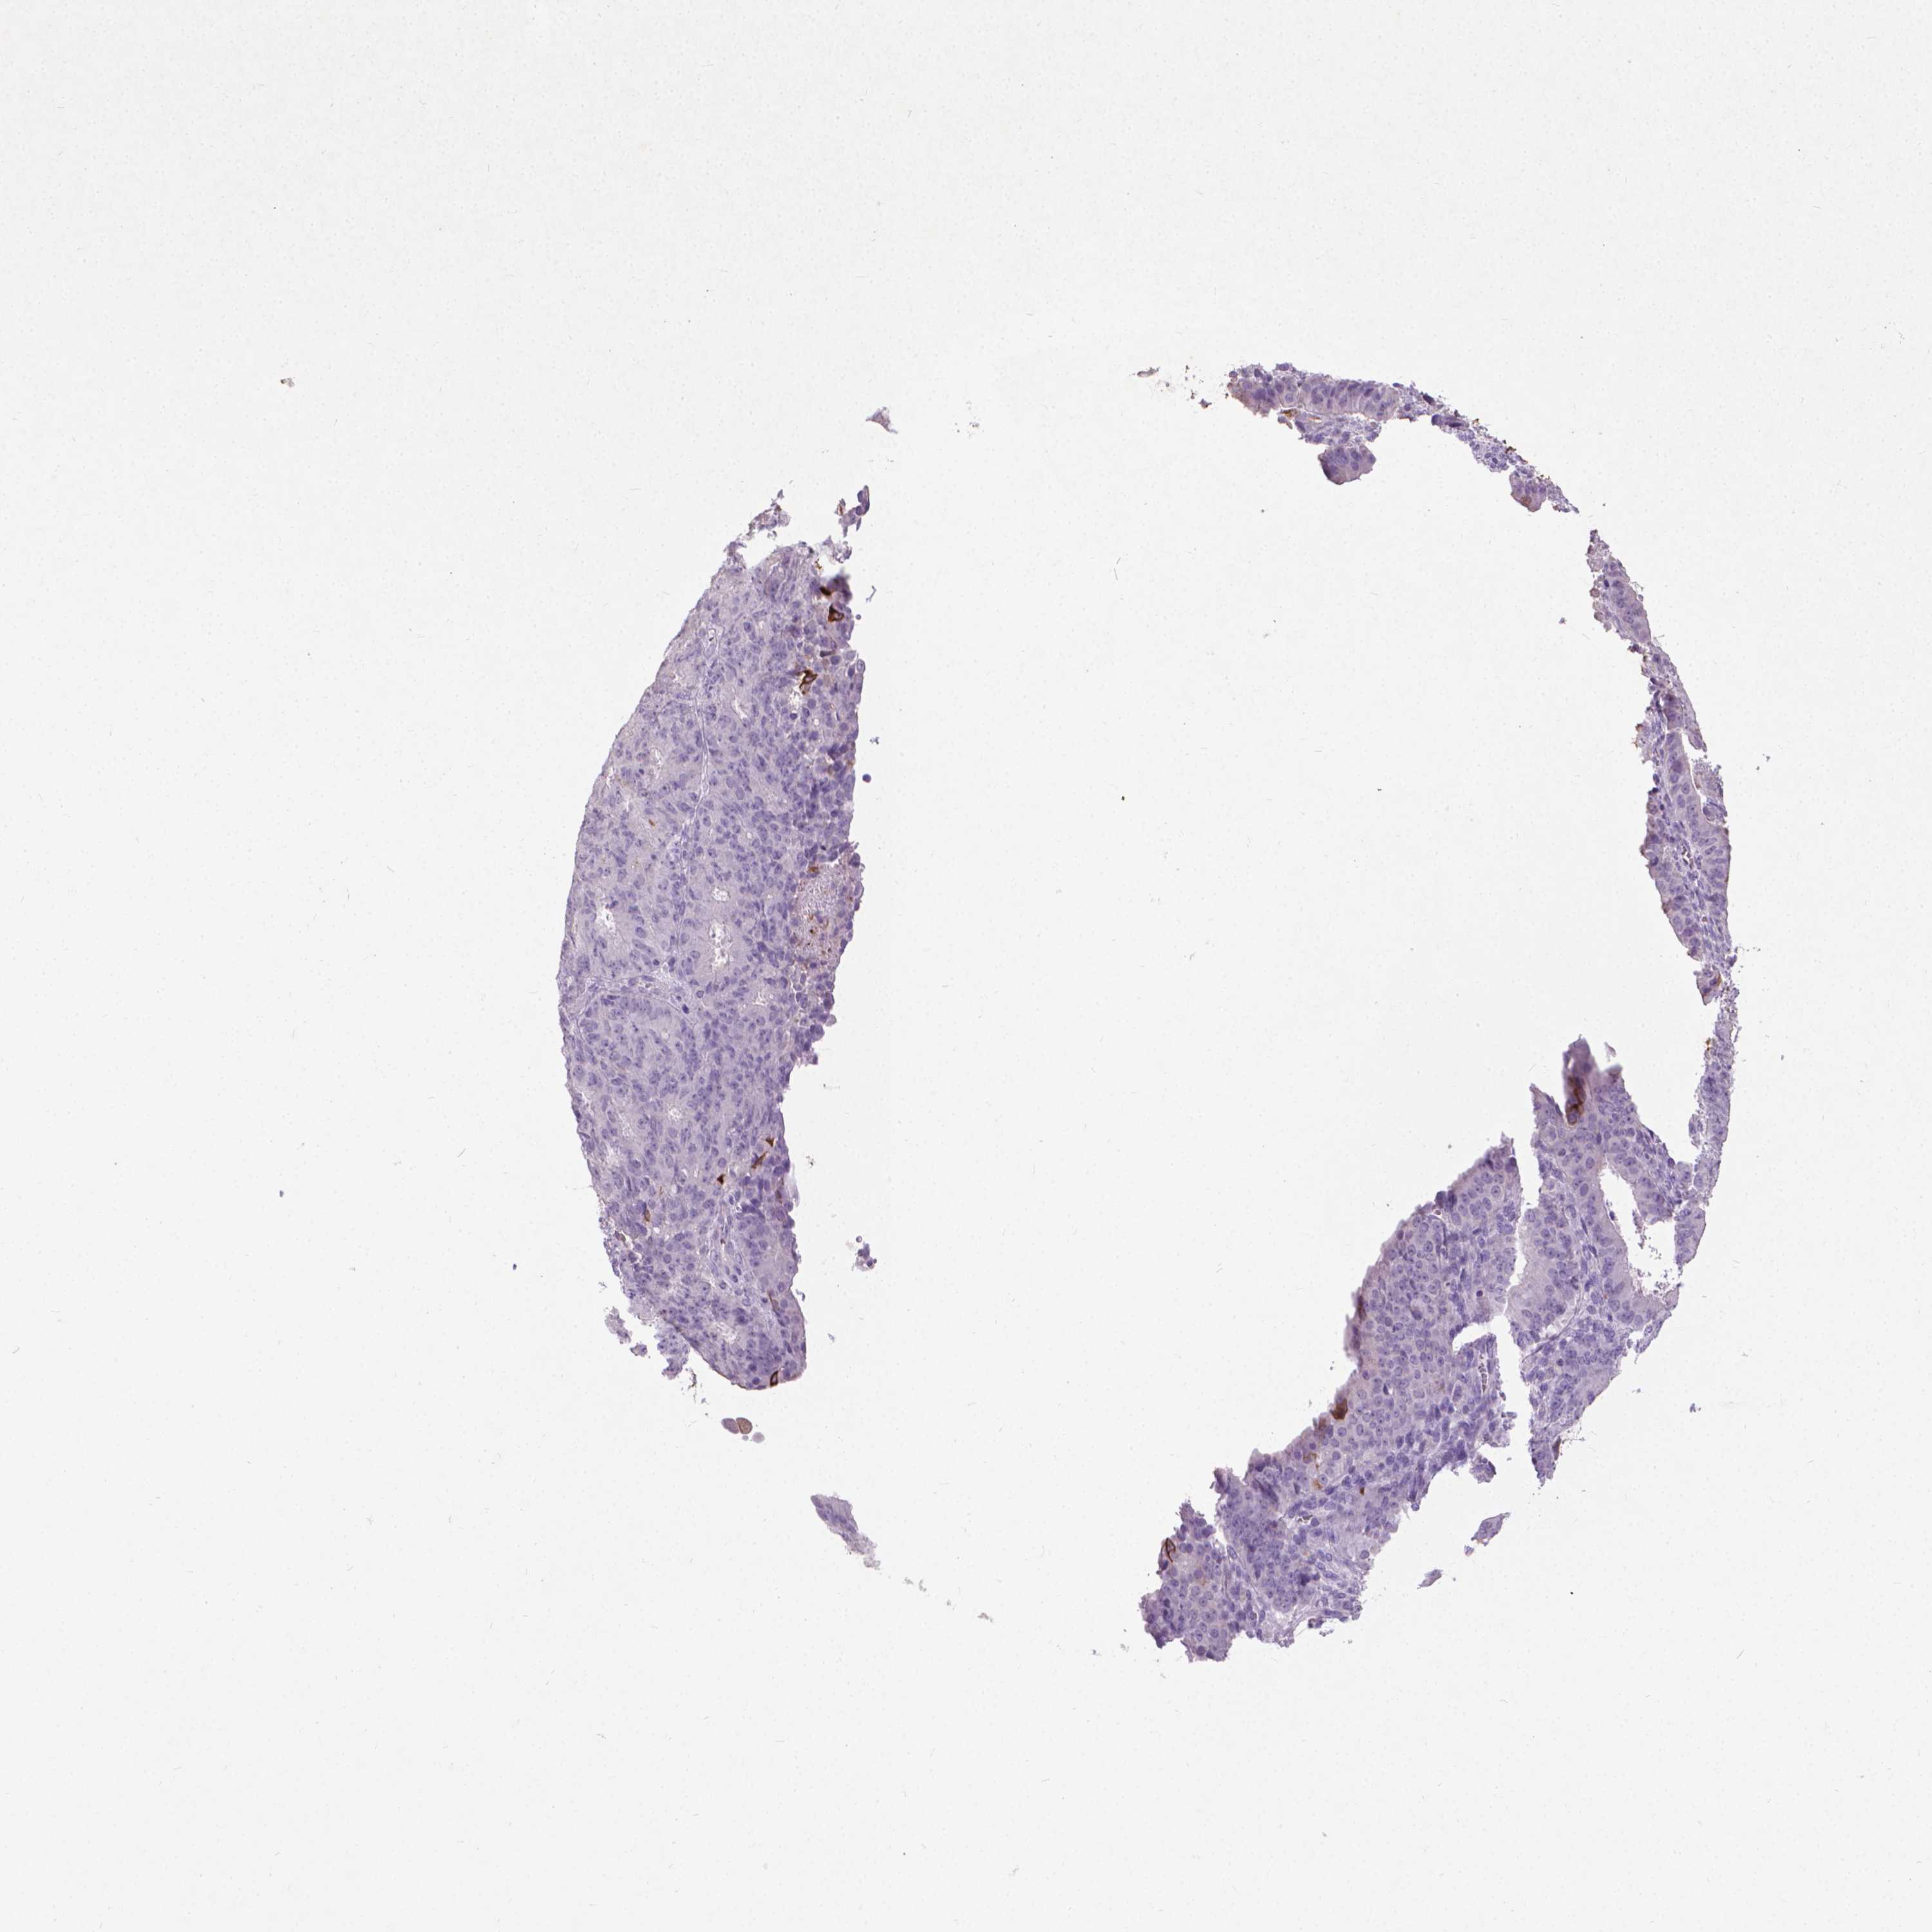

OVARIAN CANCER - Protein expressioni

A mouse-over function shows sample information and annotation data. Click on an image to view it in a full screen mode. Samples can be filtered based on level of antibody staining by selecting one or several of the following categories: high, medium, low and not detected. The assay and annotation is described here.

Note that samples used for immunohistochemistry by the Human Protein Atlas do not correspond to samples in the TCGA dataset.

Antibody stainingi

Antibody staining in the annotated cell types in the current human tissue is reported as not detected, low, medium, or high, based on conventional immunohistochemistry profiling in selected tissues. This score is based on the combination of the staining intensity and fraction of stained cells.

Each image is clickable and will lead to virtual microscopy that enables deeper exploration of all samples and also displays staining intensity scores, fraction scores and subcellular localization as well as patient and tissue information for each sample.

Antibody HPA059479

Antibody CAB000027

Antibody CAB000129

Antibody CAB080101

Carcinoma, endometroid